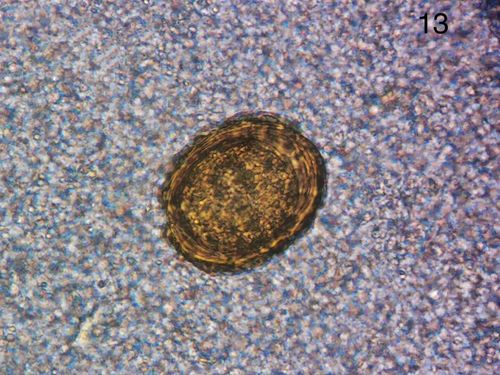

绕虫卵图片,蛲虫和蛔虫的区别图片

寄生虫虫卵图片

蛲虫虫卵图片及特点

蛔虫虫卵图片

钩虫卵图片

蛲虫卵图片